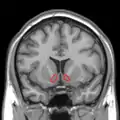

MRI coronal slice showing nucleus accumbens outlined in red

Nucleus accumbens highlighted in green on coronal T1 MRI images